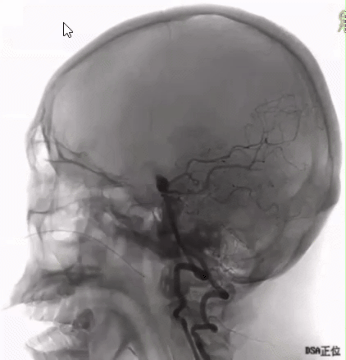

术前影像检查

基底动脉分叉部宽颈动脉瘤,伴有子囊。

根据测量:动脉瘤瘤体平均宽度为7.5mm,瘤体最小高度5.6mm。